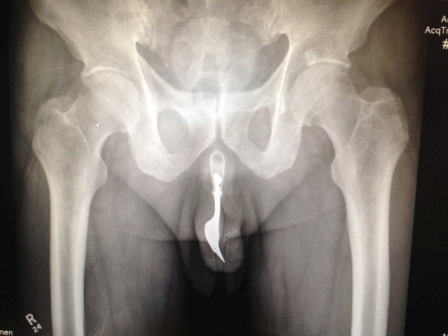

Mereka akhirnya berhasil mengangkat benda yang terbuat dari bahan stainles steel tersebut dengan menggunakan pelumas dan forsep, sementara sang pasien dibius. "Itu jelas bahwa pikiran manusia tak terbatas dan sangat kreatif," tulis mereka dalam International Journal of Surgery Case Reports.

A 70-year-old man has had a 4in fork removed from his penis after it became lodged there during a sexual act, it has been revealed.

They eventually managed to retrieve the object after using a large amount of lubrication and forceps, while the man was given a general anaesthetic.